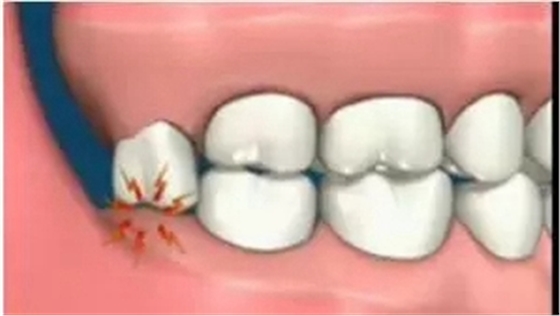

因萌出空間不足,導(dǎo)致智齒萌出不全而異位或阻生,牙冠部分露出牙齦,部分被牙齦覆蓋。

這種智齒的牙體與牙齦之間形成一個(gè)狹窄較深的盲袋,容易嵌入并積存食物碎屑和細(xì)菌,刷牙時(shí)難以清凈到這個(gè)部位,加之冠部牙齦易因咀嚼食物而損傷,形成潰瘍。當(dāng)全身抵抗力下降、細(xì)菌毒力增強(qiáng)時(shí),就可能引起牙冠周?chē)M織炎癥,出現(xiàn)明顯的疼痛、牙冠周?chē)浗M織發(fā)炎紅腫、齦瓣邊緣糜爛、張口困難等癥狀。